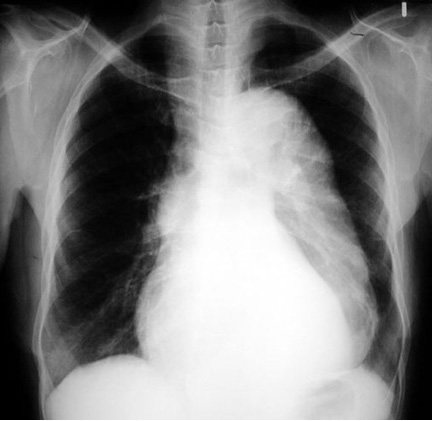

Aortic Dissection CXR

Widened mediastinum

Inlet to outlet shadow on left with wavy margin

Radiologic Criteria for dissection in plain chest radiograph:

• Demonstrates mediastinal widening in around 63% of patients with an aortic dissection, however this finding is nonspecific and is seen in many normal age-matched controls.

• Internal displacement of aortic calcifications by 1 cm or more and disparity in size between the ascending and descending aorta are more specific for aortic dissection, especially when they represent a new finding compared to old films.

• Inlet to outlet shadow with wavy margins

• Frequently a left pleural effusion is seen.

• Localizes bulging of the aortic contour indicating the likely site of origin of a dissection.